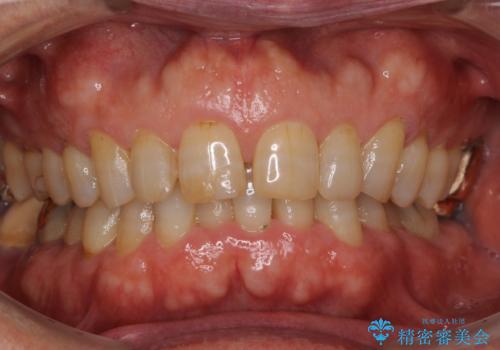

- 前歯のすきっ歯を気にして来院された患者様です。

矯正かオールセラミックか、治療の選択がありましたが、ご年齢や色の濃い点を考慮してオールセラミッククラウンにて補綴することとしました。

折角なのできれいに仕上げたいとのことで、オーダーメイドタイプのクラウンを選択されました。色調を周りのご自身の歯と合わせることができるため、自然な仕上がりをご希望の方におすすめです。